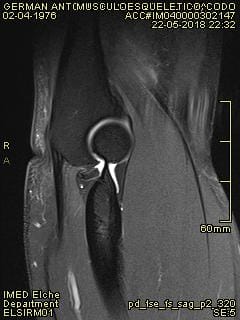

¿Quién me puede echar una mano con una resonancia magnética de tedon de bíceps en codo?

la mutua no se pone de acuerdo con el hospital y me tienen mareado, ¿alguien me echa una mano para saber lo que puedo tener en el codo? Dispongo de más fotos, pero no se cual indicar para que puedan ver algo. Muchas gracias de antemano